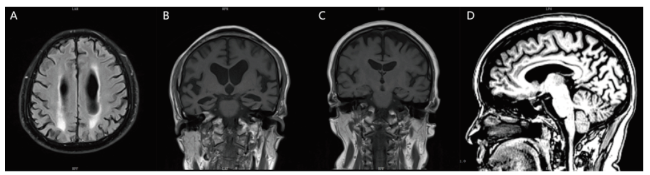

有12例患者的头颅结构影像表现为不同程度的额颞顶叶皮层萎缩,多为不对称性的,其中有8例患者出现不同程度的脑白质损害(图A)。所有患者均完成头颅MRI显影的内侧颞叶萎缩(MTA)视觉评分[5],有10例患者出现海马萎缩(图B);有4位患者的海马是正常的(图C),但均出现后扣带沟、顶枕沟增宽,后方扣带回和楔前叶萎缩的顶叶萎缩(图D);有1例患者未见明显的脑萎缩。

图A 病例8患者头颅MRI T2 FLAIR像脑白质损害融合成大的病灶;图B 病例8患者头颅MRI T1像冠状位见海马重度萎缩,MTA评分4级;图C 病例4患者头颅MRI T1像冠状位见海马正常,MTA评分0级;图D 病例4患者头颅MRI T1像失状位见后扣带沟、顶枕沟增宽,扣带回后方和楔前叶萎缩。

Fig.A T2-weighted Flair MRI images showing white matter lesions fused into large lesions in Case 8;Fig. B T1-weighted MRI images showing severe hippocampus atrophy in coronal position, and MTA score is 4 in Case 8;Fig.C T1-weighted MRI images showing normal hippocampus in coronal position, and MTA score is 0 in Case 4;Fig.D T1-weighted MRI images showing the posterior cingulate groove, parieto-occipital groove widening, cingulate back posterior and anterior cuneiform atrophy in sagittal position in Case 4.

不同的患者磁共振的表现差异较大,缺乏特异性;患者评估时的年龄越小,神经心理量表得分越高的,其磁共振的表现肉眼看有可能是正常的或者是只有轻度的顶叶萎缩。晚发型AD在结构核磁的表现主要是内侧颞叶萎缩,临床上常用的是目测法,即内侧颞叶萎缩(MTA)视觉评分:通过MRI冠状位,对萎缩的海马进行分级,从正常到严重萎缩分为0~4级[5]。MTA对鉴别晚发型AD的敏感性和特异性较高[17],但对于鉴别早发型AD缺乏特异性;早发型AD相对于晚发型AD,内侧颞叶萎缩不明显,而顶叶、外侧颞叶的改变更加突出[18]。可以对一个高度怀疑阿尔茨海默病的患者进行随访复查,观察内侧颞叶萎缩是否有进展;对于年轻的患者,需要注意有没有以后扣带沟、顶枕沟增宽为表现的顶叶萎缩。